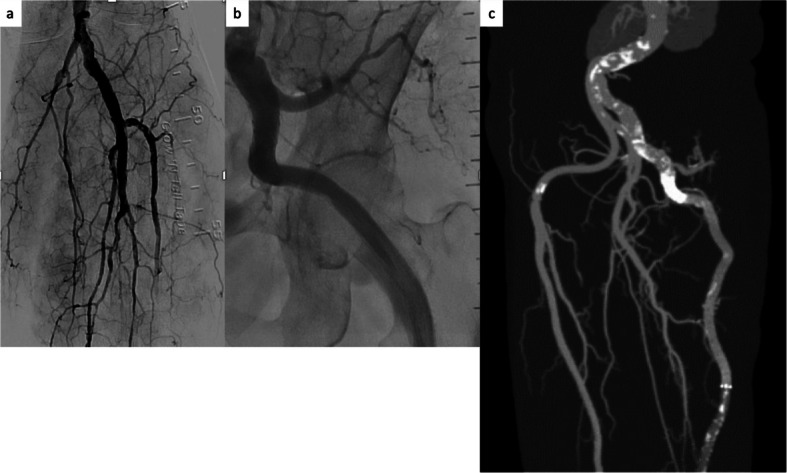

Case presentation: This case report details the treatment of two women (aged 89 and 82 years) with ALI associated with PSA. In both cases, reperfusion was achieved without CDT and stent grafts were deployed across the PSA aneurysm. The final angiogram showed that the PSA aneurysms had disappeared, and the vessel runoff was maintained. Both patients were successfully discharged from the hospital and experienced no complications over the next 6 months.